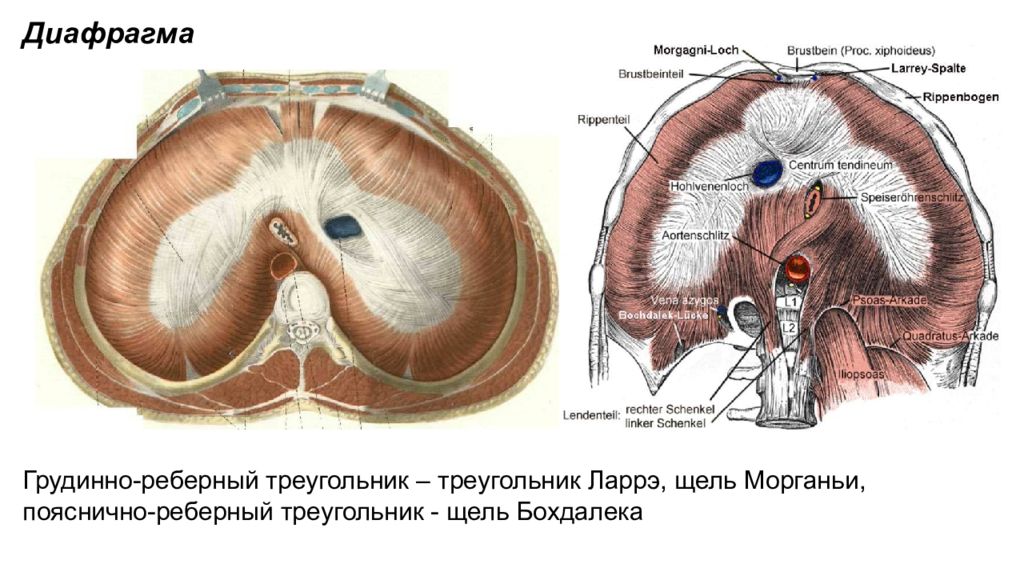

Анатомия диафрагмы и треугольника Бохдалека

Раздел: Визуальный дайджест